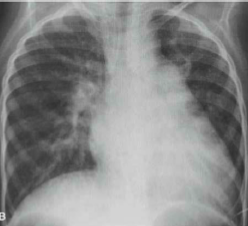

Com base no raio-x ilustrado a seguir, qual patologia é mais provável de ser encontrada?